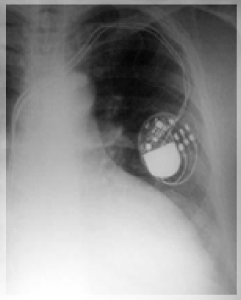

VALORACIÓN DE MARCAPASOS Y DESFIBRILADORES

¿En qué consiste la valoración de marcapasos y desfibriladores? Consiste en la lectura por telemetría (“a distancia”), mediante el uso de un programador, de los parámetros con los cuales está programado un marcapasos o un cardiodesfibrilador. Además de los parámetros de funcionamiento, la interrogación también provee información de las señales propias del paciente, así como diferentes eventos almacenados por el dispositivo. Estos eventos dan información útil sobre el ritmo cardiaco del paciente y permiten, en muchos casos, tomar decisiones con respecto al mismo dispositivo o al tratamiento farmacológico.